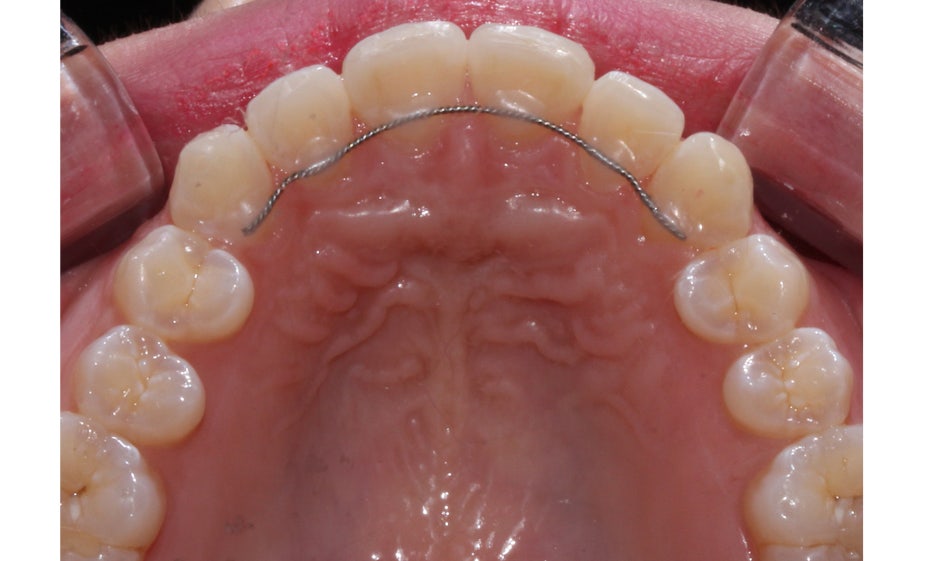

뻐드렁니교정 전 상악의 교합면을 보면

11번치아(좌측 중절치)가 입술 방향으로

튀어나와 있는 모습을 확인할 수 있는데요,

악궁의 길이가 짧은 경우 치아가 배열될 수 있는

공간이 부족해지면서 위와 같은 증상이 나타날 수 있습니다.

뻐드렁니교정 후 상악 교합면을 보면

서로 겹쳐져 있던 중절치가 가지런하게

배열된 것을 확인할 수 있는데요,

전체적인 안모의 형태도 이상적인

U-라인으로 바뀌어 정돈된 느낌입니다.